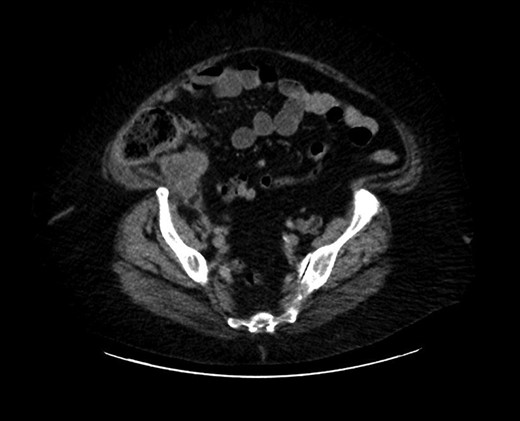

The patient had a previous admission 4 weeks back with the same kind of complaint, but according to the patient, went for an outpatient follow-up upon with her OB/GYN doctor. Upon presentation with at the outpatient department, with the wage ongoing right-sided discomfort for few weeks, the physician placed an order for a computerized tomography (CT) scan which identified a mass-like density in the base of the cecum with extra luminal soft tissue thickening and probable developing phlegmon (Fig. 1) not yet percutaneously drainable measuring (47 × 37 mm). She was advised to go to the emergency department. During the admission, she spent 5 days in the hospital as an inpatient and was treated for a phlegmonous abscess of the appendix, as per the CT indicated. During the hospital course, she was treated with Flagyl 500 mg IV TID and Aztronam 1 g TID for 5 days and, during discharge, she was given PO Flagyl Q8H and PO Bactrim Q12 H for another 9 days. She was advised to follow-up with the surgical outpatient services to schedule an interval appendectomy with the resolution of the inflammation. She soon developed a recurrent episode of abdominal pain, starting 3 weeks post-discharge and was re-admitted with worsening reproduction of the prior symptoms.

Cross section of abdominal computed tomography showed an appendiceal tumor.